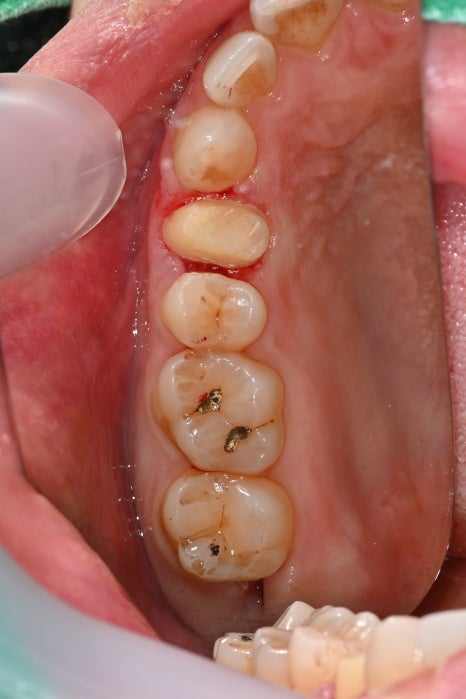

Second photo: Upper molar photo taken at the initial visit. The caries area and the broken tooth condition are visible.

Third photo: Lower molar photo taken at the initial visit. Caries had progressed in two lower molars, and inlay treatment was needed.